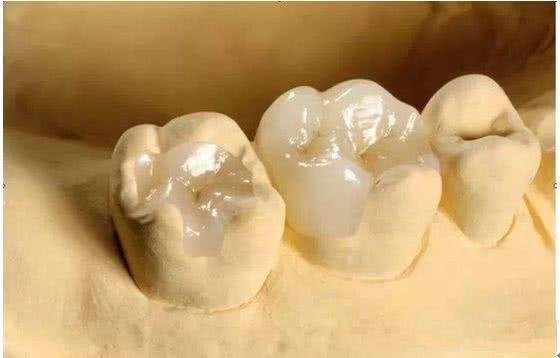

利用纳米材料填补

假如牙齿虽然裂了,但是裂纹小,可以使用纳米材料填充,当然,树脂填充也可以,利用它们将牙齿裂纹填充好就可以了。